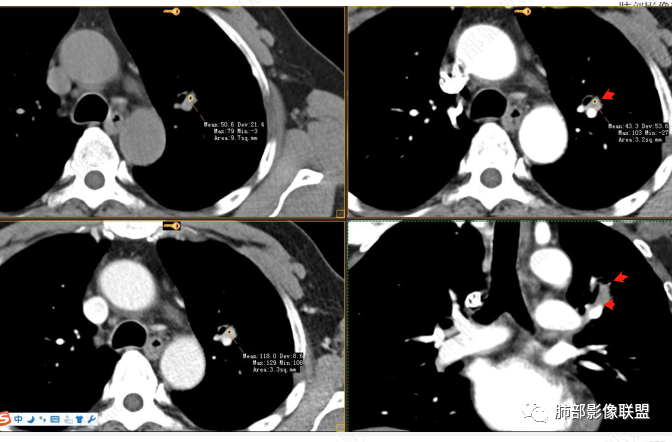

男性,肺结节3年,发现逐渐增大,影像表现,左肺舌段结节,边缘可见磨玻璃密度影,内部走形下舌段支气管变窄,增强呈持续强化,首先考虑肺腺癌,鉴别炎性肉芽肿,真菌/隐球菌。

中老年男性,发现结节,影像表现,左肺上叶结节,实性部分有膨胀性生长,边缘可见磨玻璃影,似清晰似不清晰,病灶与支气管关系密切,部分支气管似狭窄及僵硬,增强病灶强化明显,考虑腺癌(粘液性腺癌)鉴别炎性肉芽肿。

实性结节边缘伴晕,晕边界模糊,缺乏膨胀和收缩力,但复查增大,高强化。考虑1、炎性肉芽肿,隐球。2、肿瘤,淋巴上皮瘤样癌,腺癌。

左肺上叶尖段支气管旁结节伴磨玻璃影,磨玻璃影边缘模糊,支气管走形正常,病变无明显分叶及毛刺,收缩不明显,增强呈延迟高强化。先考虑炎性肉芽肿。肿瘤待排。

左肺上叶支气管旁结节伴磨玻璃影,磨玻璃边缘略模糊,沿支气管走行,明显不均匀延迟强化,3年逐渐增大,考虑腺癌,鉴别淋巴增殖病变,炎性肉芽肿

中年男性,查体发现,左肺上叶靠近支气管旁实性结节,周围有磨玻璃影,边界清,密度高,明显强化,三年缓慢进展,考虑腺癌,鉴别类癌或炎性肉芽肿。

中老年男性,左肺上叶中轴区实性结节及周围磨玻璃影,磨玻璃边界似清非清,关键点2019.10-2021.10-2022.05结节持续增大,增强后明显强化。考虑恶性结节可能大,腺癌(黏液腺癌)?鉴别炎性结节。

361度:

2、病灶以实性密度为主,前、外侧蔓延,GGO部分边界清楚,部分欠清

支气管未见受明显侵犯,未见阻塞,壁增厚,狭窄或扩张。

软组织+重建;病灶实性部分不是类圆形,密度相对均匀柔和。

肺门区病灶与支气管关系不密切,强化显著、磨玻璃晕等等容易想到的是肺腺癌。而不首先考虑与支气管密切相关恶性肿瘤,如鳞癌、类癌、粘液表皮样癌等等。